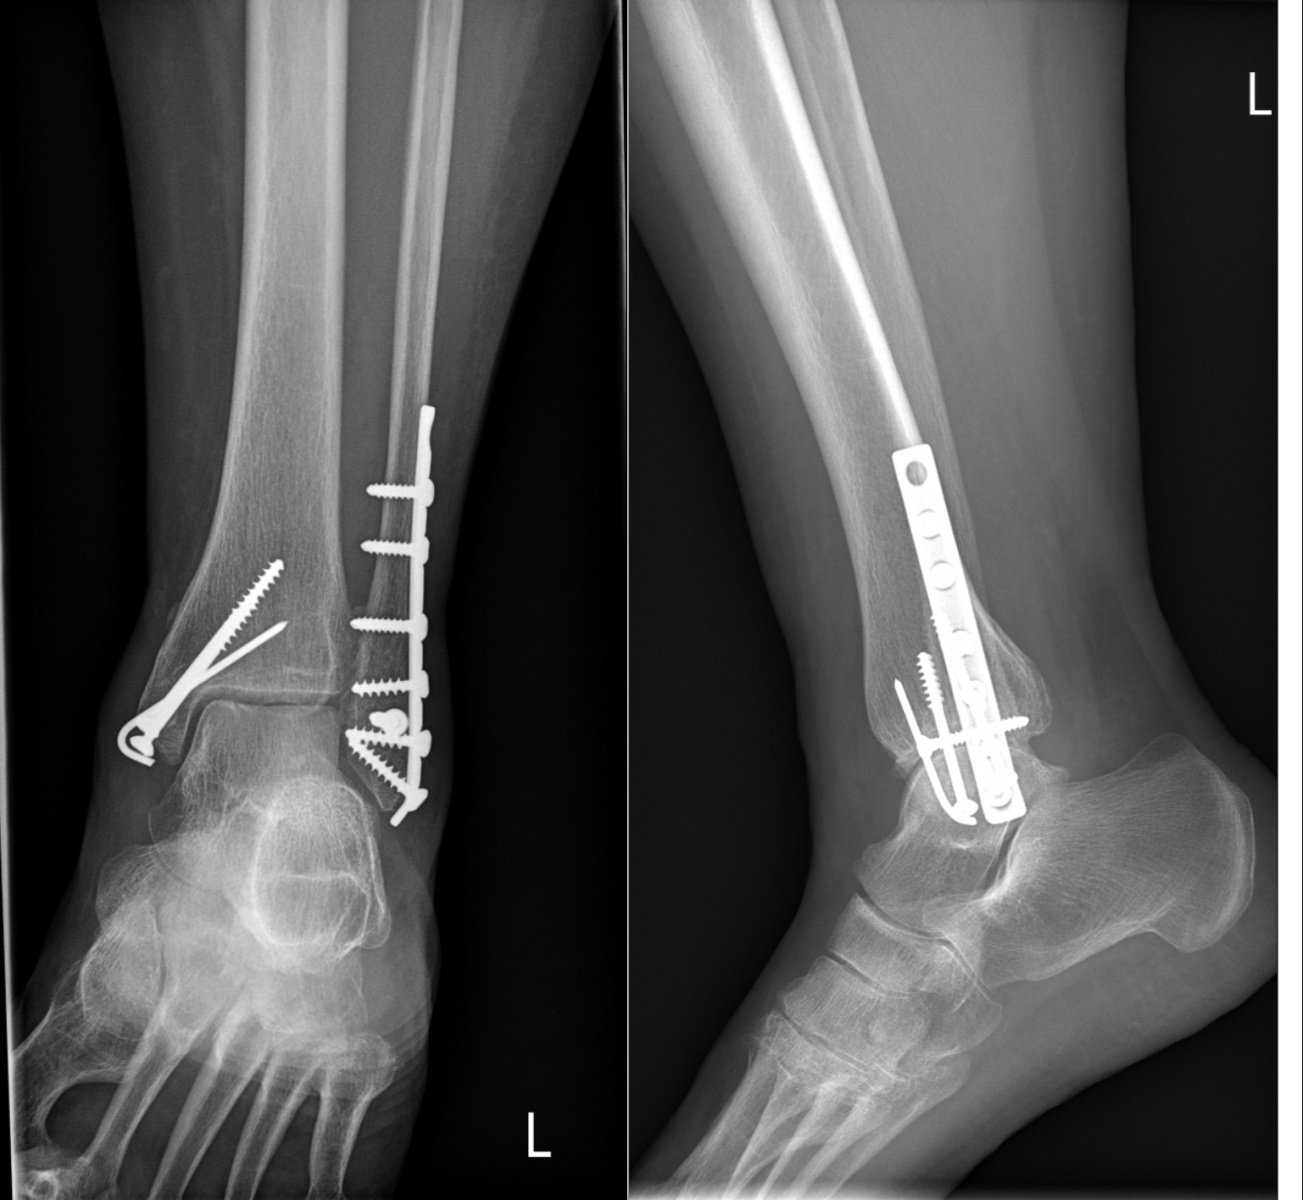

Ukázky RTG snímků